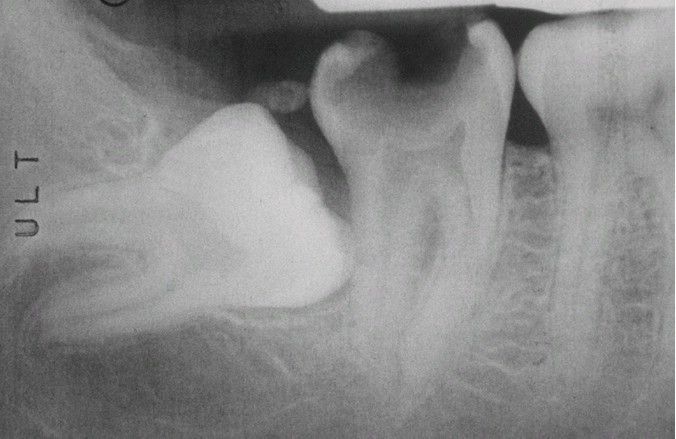

Eruption sequestrum

A radiopaque fragment of sequestrating bone can be seen overlying an impacted third molar.